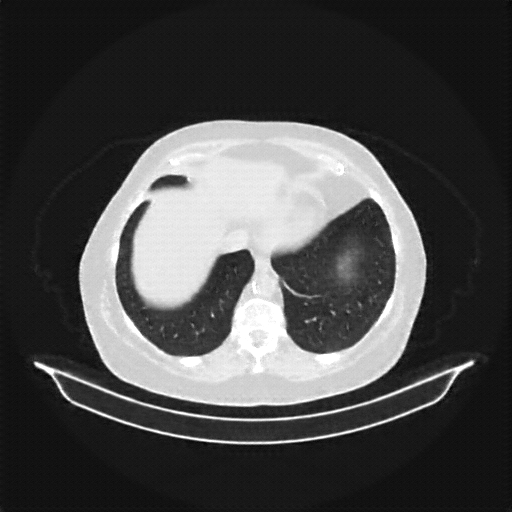

Image Grid

4Γ—3 grid: Rows show different image types (Original NATIVE, Reconstructed NATIVE, Original VENOUS, Generated VENOUS), Columns show windowing techniques (No Window, Lung Window, Mediastinum Window)

Original VENOUS CT scan

Full window (WL 1023.5, WW 4095 β†’ Low βˆ’1024, High +3071)

Actual HU range: [-1024.0, 1092.0]

Mediastinum window (WL 40, WW 400 β†’ Low βˆ’160, High +240)

Actual HU range: [-160.0, 240.0]